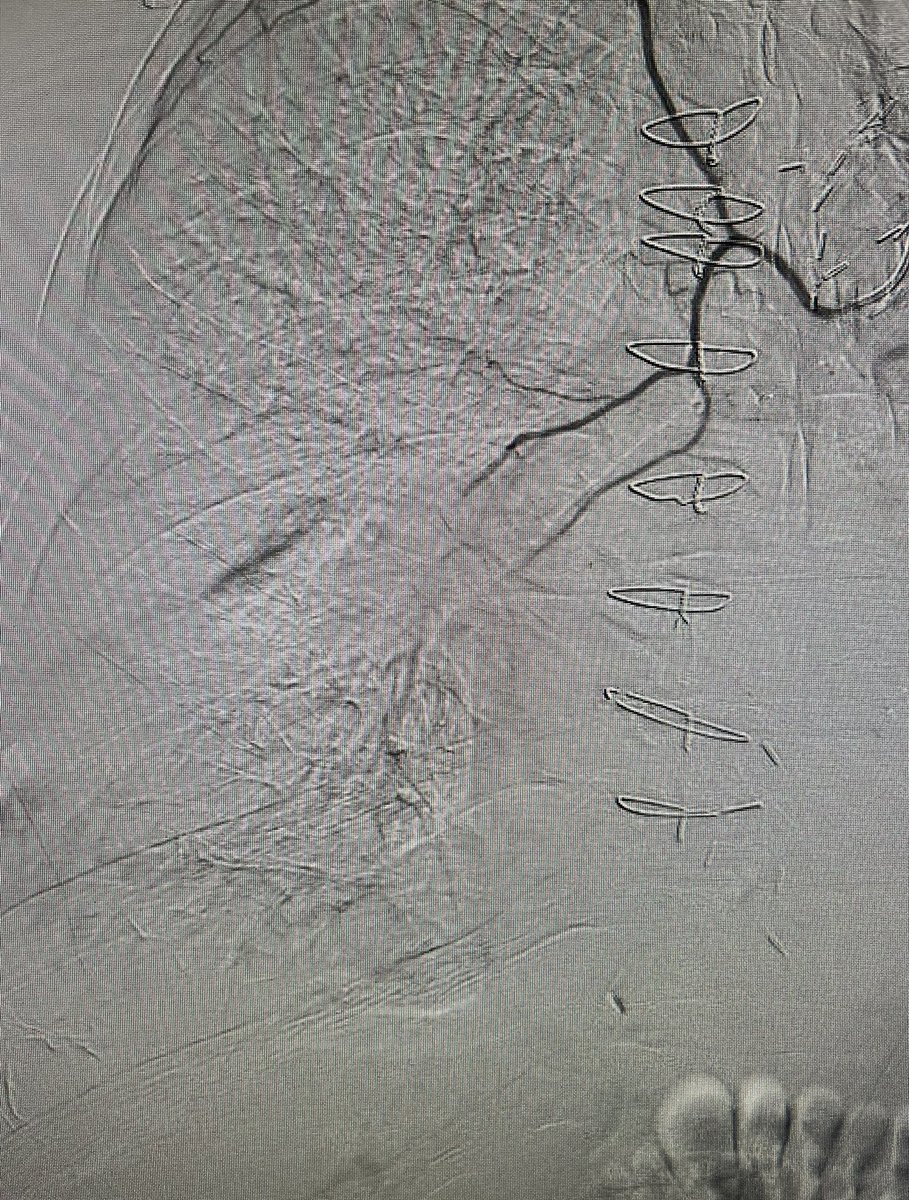

Post liver txp+TIPS referred for TJLB. Would anyone try TJ approach? Transfem transcaval (TFTC) works too and very quick! 1) Add another curve to metal cannula, 2) aim lateral, 3) make sure needle doesn’t go thru TIPS. The Dotter Institute Montefiore Radiology SIR ECS SIR RFS

Post liver txp+TIPS referred for TJLB. Would anyone try TJ approach? Transfem transcaval (TFTC) works too and very quick! 1) Add another curve to metal cannula, 2) aim lateral, 3) make sure needle doesn’t go thru TIPS. <a href="/dotter_IR/">The Dotter Institute</a> <a href="/MontefioreRAD/">Montefiore Radiology</a> <a href="/SIR_ECS/">SIR ECS</a> <a href="/SIRRFS/">SIR RFS</a>